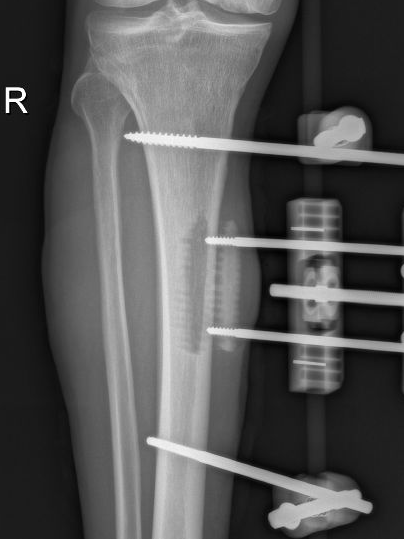

4月23日,贵州航天医院第58次晨读会由我院骨科副主任医师张艳金作学术交流,他以“加速康复指导下的快速手术”为题,详细讲解了老年股骨粗隆间骨折与儿童四肢骨折的临床诊疗难点,结合加速康复外科(ERAS)核心理念,重点阐述了ERAS理念在两大人群中的创新实践,实现患者入院后6至24小时内即可接受手术治疗。针对老年髋部骨折患者,提出通过多学科协作(MDT)与微创手术优化围术期管理,在确保安全前提下缩短术前等待时间,实施精准化麻醉及术后康复方案,可有效降低并发症发生率、改善患者生活质量和预后效果。在儿童骨折领域,强调微创术式与心理干预并行的双轨策略,既减少手术创伤对骨骼发育的影响,同时关注患儿心理疏导,实现生理功能与心理健康同步康复。并通过典型案例的影像学资料与随访数据,直观展示了ERAS理念指导下骨科治疗模式的创新成果。 贵州航天医院骨科 专家简介 赵学平 中共党员,骨科党支部书记、主任,主任医师 临床擅长:从事骨科临床工作30余年,对骨科常见疾病的诊治具有丰富的临床经验。 世界中医药联合会脊柱康复专业委员会常务理事,中华中医药学会整脊分会常务委员,中国中西医结合学会骨伤科分会肢体矫形功能重建与康复专家委员会常务委员,中国研究性医院学会骨科创新与转换专业委员会关节外科学组保髋工作委员会常委,中国康复技术转化及发展促进会骨外科与康复技术转化专业委员会常务委员,泛珠三角区域运动医学联盟(PPRD-SMA)理事会常务理事,中国研究型医院学会运动医学专业委员会委员,贵州省中医药学会整脊分会副主任委员,贵州省中西医结合学会银质针专业委员会副主任委员,贵州省康复医学会骨与关节专业委员会常务委员,贵州省人民医院骨科专科联盟常务理事,贵州省康复医学会骨内科专业委员会常务委员,中华医学会贵州省骨科学会委员,贵州省康复医学会脊柱脊髓专业委员会常务委员,贵州省运动医学分会委员,贵州省康复医学会骨与软组织肿瘤专业委员会委员,遵义市医学会创伤分会副主任委员,贵州省康复医学会骨内科专业委员会遵义地区分会常务委员,遵义市医疗事故鉴定、伤残鉴定、工伤鉴定、司法鉴定专家。 长期从事骨科临床研究及教学工作,在国家级、省部级杂志发表论文20余篇,SCI论文2篇,参与主编骨科专著2部,主持省部级科研项目2项,参与指导省部级、市级科研项目6项。 陈明勇 骨科副主任,副主任医师 临床擅长:从事创伤骨科工作约20年,对骨缺损、骨不连、骨肿瘤、肢体畸形等的肢体矫形重建及功能重建,慢性化脓性骨髓炎的根治治疗、糖尿病足的保肢治疗、快速康复理念(ERAS)下的老年骨折的诊治,四肢复杂骨折的诊治,四肢骨折等微创手术治疗具有丰富的临床经验。 2004年毕业于遵义医学院临床专业,曾在中国人民解放军总医院、广西医科大学第一附属医院、上海第六人民医院骨科进修。中国中西医结合学会骨伤科专业委员会横向骨搬移治疗糖尿病足及微血管网再生学组首届委员,遵义市医学会创伤分会常务委员。 瞿 辉 中共党员,骨科副主任医师 临床擅长:对骨科的常见病、关节外科、脊柱外科及运动医学疾病的诊治具有丰富的临床经验,熟练掌握骨科手术操作技术。 毕业于遵义医学院临床医学系,2005年前往广州中山大学第一附院骨显微医学部进修学习,2011年前往成都华西医院进修学习,并多次在省内外学习骨科相关知识,是中华医学会骨科分会会员。 赵兴东 骨科主任医师 临床擅长:擅长骨科的常见病及各种创伤、四肢骨折创伤修复、骨感染、手足疾病的诊治和手足体表畸形的矫形整复,熟练掌握骨科四肢骨病及创伤的手术操作技术,尤其在四肢关节复杂性损伤、手足外伤、组织缺损创面、难治创面的皮瓣修复方面及平足、高弓足矫形方面及四肢慢性疼痛诊治、康复方面具有丰富的临床经验。 硕士研究生,毕业于遵义医学院临床外科系,2015年前往山东省立医院手足外科进修学习;遵义市医学分会创伤分会第一、二届委员,遵义市手外科医学会第二委届员会常务委员;在省级及省级以上期刊发表文章9篇,参编著作2部,参与主持并完成市级课题1项,参与市级课题2项、省级课题1项。 张艳金 中共党员,骨科副主任医师 临床擅长:从事骨外科工作16年,对复合伤、多发伤的救治、四肢骨干骨折、关节周围骨折、骨肿瘤、骨髓炎等诊治具有丰富的临床经验。 中共党员,硕士研究生,2006年本科毕业于山西医科大学第二临床医学院,2011年研究生毕业于北京军区总医院;在“老年COPD患者合并髋部骨折的诊治”国际合作课题组研究两年,在老年髋部骨折的诊治方面具有丰富的经验,并发表论文6篇;主持遵义市级课题1项,承担遵义医科大学的临床教学工作,获得遵义医科大学优秀带教老师荣誉。编撰有《骨科疾病诊疗精粹》一书,开展2项新技术,编撰地方规范《务川自治县创伤骨科常见疾病诊疗规范》一书。 张俊凯 骨科副主任医师 临床擅长:从事骨科临床工作28年,对创伤骨折、骨感染、骨缺损、骨不连等外科诊治,四肢骨折的微创手术治疗,四肢复杂骨折(如关节内粉碎性骨折、多发骨折等)的损伤控制及手术治疗等具有丰富的临床经验。 1995年毕业于遵义医学院临床专业,2009年前往复旦大学附属医院骨科进修1年。 卢懿明 中共党员,骨科副主任医师 临床擅长:从事骨科工作18年,对创伤骨折、四肢骨折的微创手术治疗、四肢复杂骨折(如关节内粉碎性骨折、多发骨折等)的损伤控制及手术治疗,尤其是髋部骨折的PFNA等微创技术,踝关节骨折、膝关节周围骨折的Mipo微创技术等具有丰富的临床经验,开展了4项新技术,发明6项新型专利技术。 2005年毕业于遵义医学院临床专业,2017年,前往南方医科大学第三附属医院骨科进修半年,回院后运用Mipo技术对骨干骨折及干骺端骨折的治疗技术,同时积极开展骨盆骨折、髋臼骨折腹直肌外侧切口的应用;发表了多篇专业论文,经常参与省内外学术交流会授课,获得医院荣誉称号多个。 邬夏荣 骨科副主任医师 临床擅长:从事骨科工作16年,对四肢复杂骨折、骨肿瘤的诊治,尤其是足踝创伤、慢性踝关节损伤、平足症等诊疗具有丰富的临床经验。 2006年毕业于遵义医科大学临床医学专业,曾在陆军军医大学西南医院进修学习,发表多篇骨科学术论文。 余德怀 中共党员,骨科副主任医师 临床擅长:从事骨科工作10余年,对运动医学、骨关节、脊柱外科常见病、多发病的诊治具有丰富的临床经验。 硕士研究生,2011年毕业于遵义医学院临床医学专业,曾前往遵义医科大学附属医院运动医学专业进修学习;是贵州省医学会运动医学分会青年委员,西部关节镜联盟委员;发表多篇骨科学术论文。 冯 乾 骨科副主任医师 临床擅长:从事骨科工作近20年,熟练掌握骨科多发病及常见病的诊治,尤其对脊柱退变性疾病的诊断及治疗具有丰富的临床经验,主要研究脊柱微创相关治疗方式,能熟练开展椎间孔镜及UBE。 曾前往北京大学第三医院进修学习疼痛及椎间孔镜、首都医科大学友谊医院专业进修脊柱内镜;是贵州省康复医学会第三届脊柱脊髓专业委员会委员;发明专利3项、发表脊柱外科专业论文多篇。 赵小锋 中共党员,骨科副主任医师 临床擅长:从事骨科临床工作11年,对骨科常见病、多发病诊疗有较为丰富的临床经验,擅长脊柱相关疾病诊断及治疗,尤其是颈、腰、腿疼痛疾病诊断及治疗,擅长胸腰椎骨折微创经皮穿刺内固定术、经皮穿刺椎体成形术、经皮穿刺脊柱内镜下腰椎间盘摘除术、单纯开创腰椎间盘摘除术、腰椎滑脱复位椎间植骨椎融合内固定术、腰椎管狭窄减压融合内固定术及人工髋、膝关节置换术等。 2012年毕业于遵义医学院外科学专业硕士研究生,2019年参加“遵义市115医学人才精英计划”于上海交通大学第一附属医院培训学习,2023年于北京大学第三人民医院脊柱外科进修学习,曾获得遵义市优秀医师荣誉称号。 遵义市手外科第一届委员,遵义市医学会创伤分会第一届委员,遵义市医学会创伤分会第二届委员,贵州省康复医学会第三届脊柱脊髓专业会委员,遵义市医学会烧伤与整形外科学分会委员,发表论文5篇,其中国家级核心期刊1篇,SCI论文1篇,主持市级课题1项并结题,参与市级课题2项。 贵州航天医院骨科 简介 基本情况 贵州航天医院骨科组建于20世纪60年代,前身是以创伤和断肢(断指)再植闻名于世的上海市第六人民医院骨科,中国断肢(断指)再植的奠基者、中科院院士陈仲伟等著名专家、学者多次莅临科室指导医疗、教学,是贵州省最早拥有专业骨科技术科室之一,在70年代开展了贵州省首例断肢(断指)再植手术。组建50余年来,诊治患者已逾百万,挽救了无数的伤病员,成为了保障遵义地区人民群众健康的重要支撑。 经过几代人的不懈努力,今天的骨科,已由创伤骨科发展至骨病、骨肿瘤、骨结核等领域,现有脊柱外科、关节外科、四肢创伤、手足外科四个亚专科,成为了集医疗、教学、科研于一体的综合学科,是贵州省临床重点专科、遵义市临床重点专科、遵义市骨科临床医学中心、遵义市基层骨科专科联盟理事长单位。 科室目前开放床位110张,共有医护人员50余人,副高级以上专家18人,硕士研究生15人。拥有一流骨科医疗设备多台,每年不定期选派优秀技术骨干到全国各大知名医学院校进修、学习、参观、交流,并邀请国内、国外知名专家教授来院进行交流、指导,通过不断引进国内外先进的诊疗技术,科室医疗技术水平稳步提升,为广大人民群众提供了优质的医疗服务。 专科特色 骨一科 (一)骨缺损、骨不连的肢体与功能重建 胫骨横向骨搬移技术治疗糖尿病足: (二)慢性骨髓炎的根治治疗 (三)肢体缺血性疾病如糖尿病足、脉管炎的保肢治疗 (四)皮瓣修复 (五)复杂创伤的治疗 (六)老年髋部骨折及小儿骨折快速手术 老年髋部骨折: 骨二科 (一)胸腰椎骨折微创经皮椎弓根螺钉固定术 (二)老年性骨质疏松性患者腰椎滑脱脊柱内固定术(骨水泥螺钉) (三)V形双通道脊柱内镜技术(VBE)腰椎融合术治疗腰椎退行性疾病 (四)老年性骨质疏松性骨折(PVP/PKP)术 (五)人工髋关节置换术 (六)双侧股骨头坏死人工全髋关节置换 (七)右侧全髋置换术后假体周围骨折翻修 (八)人工膝关节置换术 (九)人工膝关节假体松动翻修 (十)关节镜技术 传统手术切口 关节镜技术切口 诊疗范围 骨一科 1.四肢创伤、矫形。 2.手、足踝外科。 骨二科 end